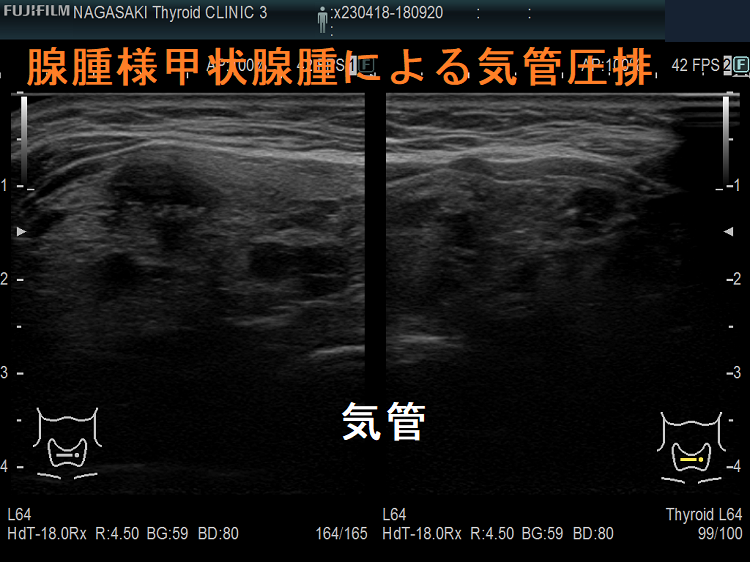

腺腫様甲状腺腫

腺腫様甲状腺腫でも咽喉頭圧排と浮腫により、閉塞性睡眠時無呼吸症候群(OSAS)を引き起こします。甲状腺全摘出で改善(J Laryngol Otol. 2012 Feb;126(2):190-5.)。

ケース③